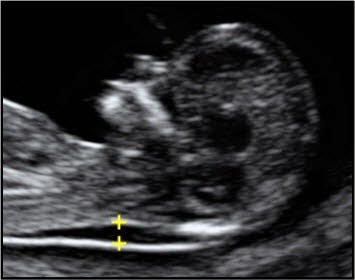

Translucența nuchală, este cel mai important marker ecografic din primul trimestru, care se asociază cu anomaliile fetale – cromozomiale, genetice, anatomice

- Efectuat în primul trimestru (nuchal scan, între 11-14 săptămâni de sarcină – cu performanța cea mai bună; rata de detecție de 92% și 3% rezultate fals pozitive în cazul sindromului Down); depistarea anomaliilor fetale severe: anencefalie, alte defecte de tub neural, anomalii cardiace, anomalii ale peretelui abdominal, anomalii renourinare, anomalii ale membrelor, anomalii ale sistemului nervos central, etc;